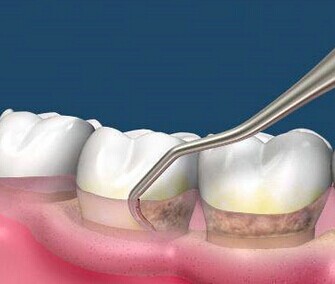

早期牙齿松动,主要是进行 牙齿洁治 (洗牙)、 龈下刮治 去除牙齿周围的牙石、菌斑等引起炎症的东西,以减轻牙齿周围的炎症。

龈下刮治可有效去除牙菌斑,缓解牙周病